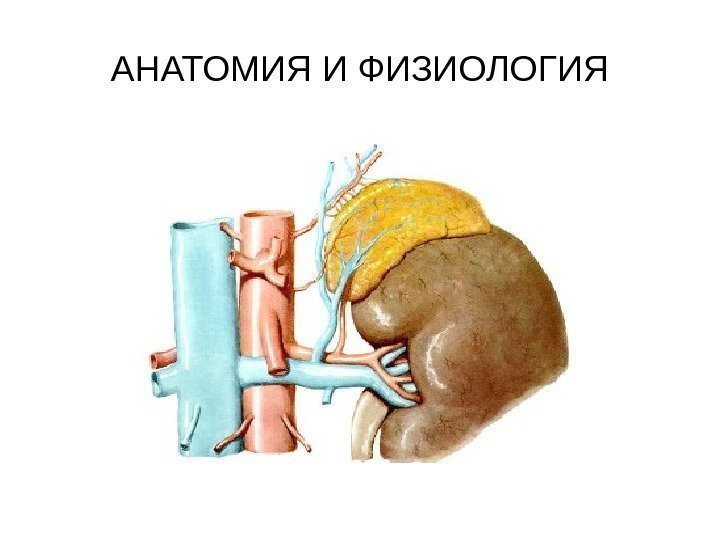

АНАТОМИЯ И ФИЗИОЛОГИЯ • Надпочечники являются парным органом, расположенным над верхними полюсами почек в забрюшинном пространстве на уровне XI-XII грудных позвонков. Масса одного надпочечника у взрослого человека составляет 12 -13 г, длина 40 -60 мм, высота 20 -30 мм, толщина (передне-задний размер) 3 -8 мм. Правый надпочечник несколько меньше левого. • Надпочечник имеет форму уплощенного спереди назад конуса. Правый надпочечник спереди напоминает треугольник с закругленными углами. Вершина левого надпочечника сглажена, и по форме он напоминает полулуние.

АНАТОМИЯ И ФИЗИОЛОГИЯ • Надпочечники являются парным органом, расположенным над верхними полюсами почек в забрюшинном пространстве на уровне XI-XII грудных позвонков. Масса одного надпочечника у взрослого человека составляет 12 -13 г, длина 40 -60 мм, высота 20 -30 мм, толщина (передне-задний размер) 3 -8 мм. Правый надпочечник несколько меньше левого. • Надпочечник имеет форму уплощенного спереди назад конуса. Правый надпочечник спереди напоминает треугольник с закругленными углами. Вершина левого надпочечника сглажена, и по форме он напоминает полулуние.

АНАТОМИЯ И ФИЗИОЛОГИЯ • У каждого из надпочечников выделяют три поверхности: переднюю, заднюю и нижнюю (почечную). Передние поверхности обоих надпочечников частично покрыты париетальной брюшиной. • Поверхность надпочечника слегка бугристая. На передней его поверхности находятся ворота, через которые из органа выходит центральная вена. • Снаружи надпочечник покрыт фиброзной капсулой, которая плотно сращена с паренхимой и отдает вглубь органа многочисленные соединительнотканные трабекулы.

АНАТОМИЯ И ФИЗИОЛОГИЯ • У каждого из надпочечников выделяют три поверхности: переднюю, заднюю и нижнюю (почечную). Передние поверхности обоих надпочечников частично покрыты париетальной брюшиной. • Поверхность надпочечника слегка бугристая. На передней его поверхности находятся ворота, через которые из органа выходит центральная вена. • Снаружи надпочечник покрыт фиброзной капсулой, которая плотно сращена с паренхимой и отдает вглубь органа многочисленные соединительнотканные трабекулы.

• Правый надпочечник расположен несколько ниже левого. правый надпочечник прилежит к поясничной части диафрагмы, — висцеральной поверхности печени и к двенадцатиперстной кишке, верхнему полюсу правой почки. Медиальный край правого надпочечника прилежит к нижней полой вене. Левый надпочечник соприкасается с аортой, хвостом поджелудочной железы и кардиальной частью желудка. Задняя поверхность левого надпочечника соприкасается с диафрагмой, нижняя — с верхним полюсом левой почки. • Поверхность надпочечника слегка бугристая. На передней его поверхности находятся ворота, через которые из органа выходит центральная вена.

• Правый надпочечник расположен несколько ниже левого. правый надпочечник прилежит к поясничной части диафрагмы, — висцеральной поверхности печени и к двенадцатиперстной кишке, верхнему полюсу правой почки. Медиальный край правого надпочечника прилежит к нижней полой вене. Левый надпочечник соприкасается с аортой, хвостом поджелудочной железы и кардиальной частью желудка. Задняя поверхность левого надпочечника соприкасается с диафрагмой, нижняя — с верхним полюсом левой почки. • Поверхность надпочечника слегка бугристая. На передней его поверхности находятся ворота, через которые из органа выходит центральная вена.

• Сосуды и нервы надпочечника. Каждый надпочечник получает до 25 -30 артерий. Наиболее крупными из них являются: • — верхняя надпочечниковая артерия (из нижней диафрагмальной артерии); • — средняя надпочечниковая артерия (из брюшной части аорты); • — нижняя надпочечниковая артерия (из почечной артерии). • Из синусоидных кровеносных капилляров формируются притоки центральной вены, которая у правого надпочечника впадает в нижнюю полую вену, у левого — в левую почечную вену. Из надпочечника выходят многочисленные мелкие вены, впадающие в притоки воротной вены. • Лимфатические сосуды надпочечников впадают в поясничные лимфатические узлы. Иннервация надпочечников осуществляется блуждающими нервами, а также ветвями чревного сплетения.

• Сосуды и нервы надпочечника. Каждый надпочечник получает до 25 -30 артерий. Наиболее крупными из них являются: • — верхняя надпочечниковая артерия (из нижней диафрагмальной артерии); • — средняя надпочечниковая артерия (из брюшной части аорты); • — нижняя надпочечниковая артерия (из почечной артерии). • Из синусоидных кровеносных капилляров формируются притоки центральной вены, которая у правого надпочечника впадает в нижнюю полую вену, у левого — в левую почечную вену. Из надпочечника выходят многочисленные мелкие вены, впадающие в притоки воротной вены. • Лимфатические сосуды надпочечников впадают в поясничные лимфатические узлы. Иннервация надпочечников осуществляется блуждающими нервами, а также ветвями чревного сплетения.